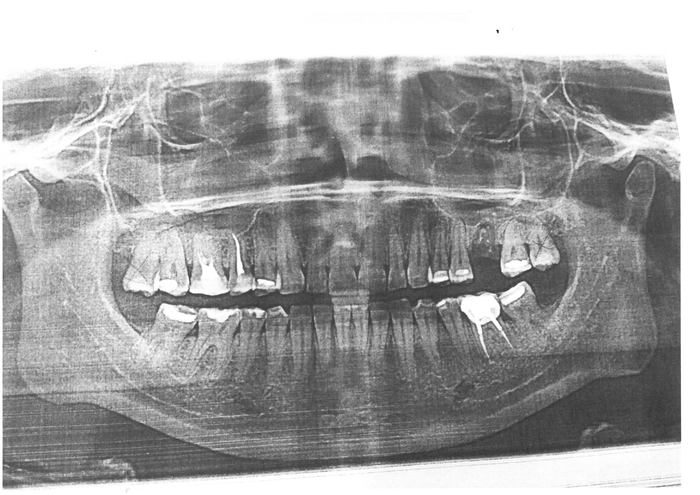

29 ноября: очередь из таких же как я в дежурный кабинет, рассказ мой о проблеме, потом рентген, потом в хирургию на обезбол (заплатил за более сильное обезболивающее, хотя мне сказали, что в моем случае я разницы не почувствую), потом сверление (не больно) и самый ад - последний кабинет, где резали десну... Да, я орал... По ощущениям - как будто без обезбола резали... Киста короче... После манипуляций отправили опять в дежурный кабинет, где сказали ехать на следующий день в клинику, где приписан... Ну ок... А полис то потерян... К вечеру выглядел значительно лучше, опухоль спадала.

1 декабря: осматривают, обеззараживают, отправляют в дежурный кабинет, где мне говорят: "А какого черта тебя не к нам сначала направили, а сразу в хирургию?". Опять осмотр, рассказ с самого начала о том, что случилось, заполнение карточки, рентген, записали на 7 декабря для установки пломбы.